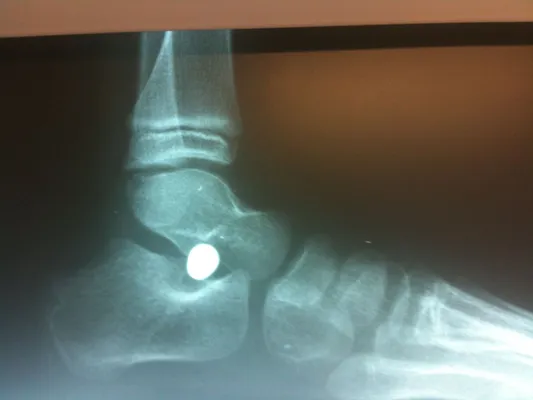

Below are x-rays of a foot pre-operatively (left) where the black line indicates and plantarflexed (downward directed) talus bone and post-surgical repair with a subtalar joint implant and lenthening of the calf muscle which allows the calcaneus (heel bone) to set underneath the talus and the implant keeps the talus from subluxing off the calcaneus and now the talus is more inline with the front of the foot (right).